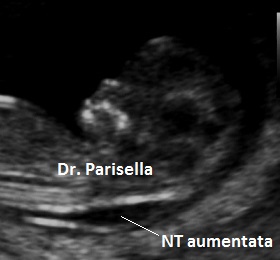

La translucenza nucale è un marker rilevabile tra le 11 settimane + 0 gg. e 13 settimane + 6 gg. di gestazione, più precisamente in un range del CRL compreso tra 45 mm. e 84 mm. Essa appare caratterizzata ecograficamente dall'accumulo sottocutaneo di fluido dietro il collo fetale nel primo trimestre di gravidanza. La Fetal Medicine Foundation (FMF) di Londra ha dettato i criteri da adottare per una corretta misurazione della NT:

Si è osservato che nei feti sani lo spessore della NT tende ad aumentare con l'incremento del CRL; di conseguenza anche i valori soglia della NT cambiano col variare dei valori del CRL: a 11 settimane con un CRL di 45 mm. i valori possono variare da 1,2 mm. (50° percentile) a 2,1 mm. (95° percentile), mentre a 13 sett. + 6 gg. con un CRL di 84 mm., i valori possono variare da 1,9 mm. (50° percentile) a 2,7 mm. (95° percentile); il 99° percentile non varia col CRL ed è circa 3,5 mm. Si intende per translucenza nucale aumentata uno spessore di NT al disopra del 95° percentile. Con un software dedicato che prende in considerazione NT, CRL, età materna e Frequenza Cardiaca Fetale (FHR), con un cut-off attualmente di 1/100 (Fetal Medicine Foundation) è possibile calcolare il rischio di anomalie cromosomiche con una sensibilità di circa il 90% ed una percentuale di falsi positivi di circa il 5%. La FHR assume notevole importanza nello screening della Trisomia 13: infatti circa l'85% dei feti con Trisomia 13 hanno una frequenza cardiaca al disopra del 95° percentile; nella Trisomia 21 solo il 15% dei feti ha un lieve aumento della FHR oltre il 95° percentile, mentre nella Trisomia 18 solo il 15% dei feti ha una lieve diminuzione della FHR al disotto del 5° percentile.

Nei feti in cui vi è una NT aumentata e cariotipo normale viene riportata una maggiore frequenza di cardiopatie congenite, displasie scheletriche, sindromi genetiche, anomalie strutturali.

Le principali anomalie congenite associate alla NT aumentata e cariotipo normale sono le cardiopatie congenite.